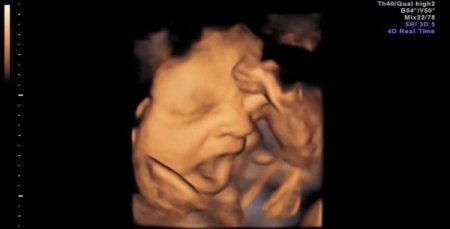

Bilim insanları, 4 boyutlu tarama yöntemiyle ultrasonda ilk kez anne karnındaki bir bebeğin esnemesini kaydetti.

İngiltere’deki Durham Üniversitesi Psikoloji Departmanı’nın, sağlık ve bilim alanında önemli makalelere yer veren PLOS ONE dergisinde yayınlanan araştırma sonuçlarına göre, 15 sağlıklı bebekte görülen yarım ağız açma hareketinin ‘esneme’ olduğu belirlendi. Doğumdan önce bebeklerin hıçkırdıkları, yutkundukları ve gerindikleri biliniyordu. Ancak esnemeleri ilk kez bu kadar net bir şekilde tespit edildi. Esnemenin, bebeğin sağlığını gözlemlemede yeni ve önemli bir ipucu olacağı düşünülüyor.

Reissland ve ekibinin gözlemi, gebeliğin 24 ve 36. haftaları arasındaki 8 kız ve 7 erkek bebekte yapıldı. Esnemenin 28. haftadan itibaren azaldığı, erkek ve kız bebeklerde önemli bir farklılığın olmadığı ortaya çıktı. CİHAN